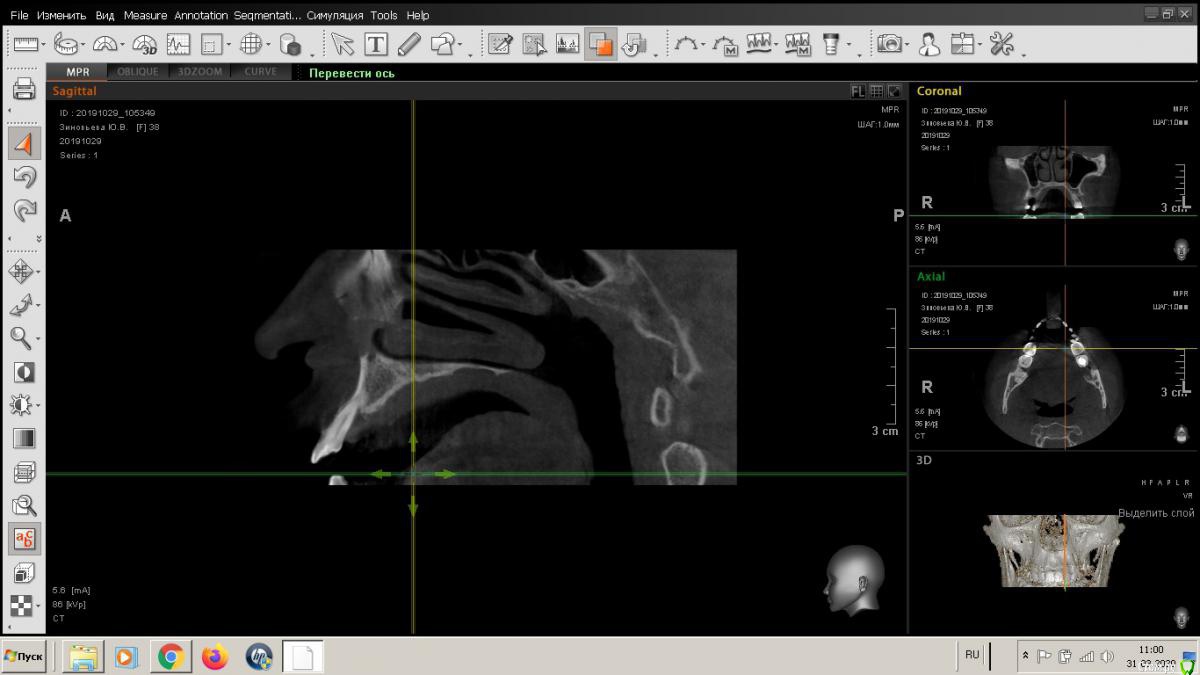

Любстер Опубликовано 31 марта, 2020 Поделиться Опубликовано 31 марта, 2020 Обратилась в октябре 2019 пациентка с жалобами на подвижность 22 зуба. Мы были третьей клиникой, куда она обратилась, везде ей говорили, что зуб сохранить нельзя, но... Также пациентка заявила, что очень боится врачей, хватает их за руки, ведет себя неадекватно, требовала общую анестезию. Мы ей рекомендовали обратиться в клинику, которая работает с анестезиологами, благополучно распрощались и забыли. И тут она опять пришла, на зубе 21 фиксирована циркониевая коронка, которую этот шатающийся 22 выдавил неведомым образом. Она эту коронку самостоятельно фиксирует обратно и так ходит. И еще она узнала, сколько стоит с общим обезболиванием процедура и решила, что лучше вернется к нам. В общем, я думаю, что с ней делать, сделать по типу консервации лунки или полноценную костную пластику с отслаиванием лоскута. Подскажите, как вы в таких случаях действуете?Записана на завтра, настаивает на операции, хотя ей было доведено, что только экстренные случаи. Я хочу от нее откреститься, главный врач говорит принять по заявлению от нее, что считает свой случай экстренным. Ссылка на комментарий

Любстер Опубликовано 31 марта, 2020 Автор Поделиться Опубликовано 31 марта, 2020 Я бы просто удалила дальше? пациентка хочет имплантацию, а кости нет, судя по кт Ссылка на комментарий